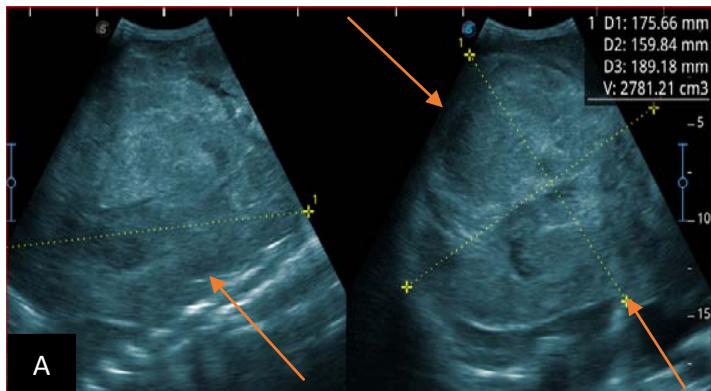

Figure 6: 9-year-old sickle cell patient, referred for abdominal bloating with significant collateral venous circulation, in whom we noted: Image A: mass, Image B: healthy renal stump, inferior polar; Image C: left transmedian extension, Image D: thrombosis of the vena cava segments: supra, retro and sub hepatic, sparing a part of the supra hepatic vena cava segment over $30~\mathrm{mm}$. Image: Ascites of great abundance, Image F: normal left kidney, Image G: splenic microcalcifications, Image H: celiac adenopathy, Image I: sub pleural pulmonary nodules with the biggest measuring $3.88 \times 3.81 \mathrm{~mm}$, Image j: left pleurisy of great abundance. Source: Dr. Frederick Tshibasu Tshienda database.